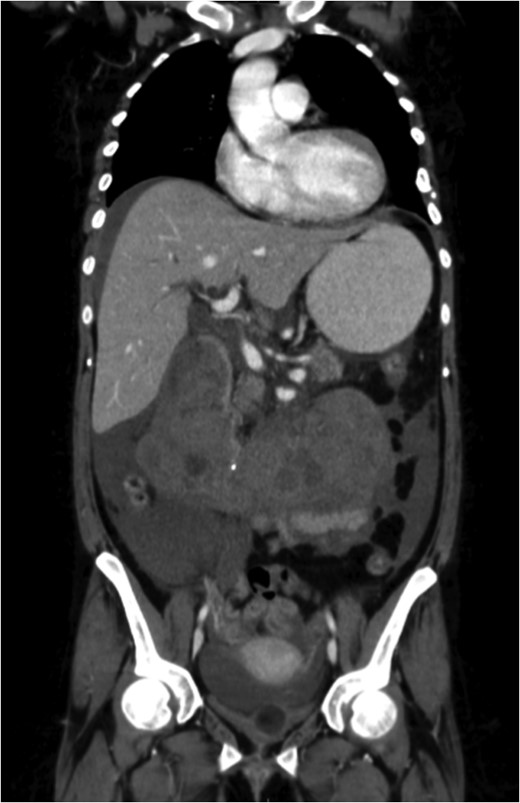

A coronal section of a venous phase abdominal CT demonstrating the end of the IVC filter strut penetrating the wall of the third part of the duodenum.

She had suffered an episode of septic pulmonary emboli with methicillin-sensitive staphylococcus aureus septicaemia. At the time of this event tomography and a gallium white cell scan revealed tilting of the IVC filter with strut perforation through the IVC and into the third part of the duodenum but no evidence of filter or bypass graft infection.